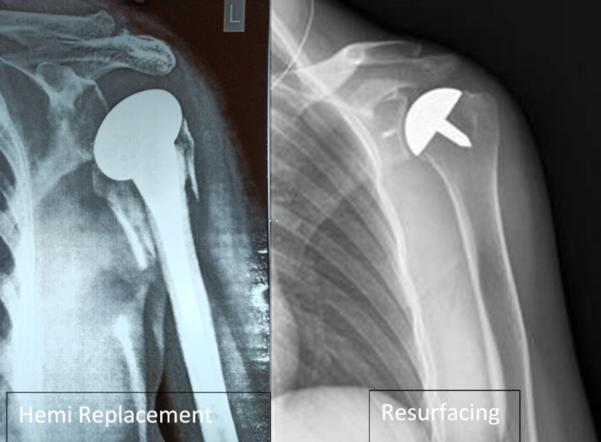

Reverse Shoulder Replacement Surgery

Reverse Shoulder Replacement Surgery By Dr. Palash Gupta Fellowship-Trained Joint Replacement Surgeon – Germany | New Zealand Yatharth Super Speciality Hospital, Model Town | Rohini Clinic, New Delhi 💡 What is Reverse Shoulder Replacement? Reverse Shoulder Replacement is an advanced surgical procedure used to treat complex shoulder problems, especially when the rotator cuff muscles are severely damaged or torn. Unlike traditional shoulder replacement (where the ball-and-socket structure is kept as-is), in reverse shoulder arthroplasty, the positions are reversed: A metal ball is placed on the shoulder socket A plastic socket is attached to the upper arm bone This unique design allows the deltoid muscle to take over the function of the damaged rotator cuff, enabling the patient to regain arm movement. 🤕 Who Needs Reverse Shoulder Replacement? This surgery is ideal for patients who have: Massive, irreparable rotator cuff tears Rotator cuff tear arthropathy (arthritis due to torn rotator cuff) Failed previous shoulder surgeries Complex shoulder fractures (especially in elderly patients) Severe shoulder arthritis with muscle dysfunction ⚙️ How is it Different from Regular Shoulder Replacement? Traditional Shoulder Replacement Reverse Shoulder Replacement Requires healthy rotator cuff Uses deltoid muscle instead Suitable for arthritis without cuff tears Best for cuff tear arthropathy or failed surgeries Ball is on upper arm, socket on shoulder Ball is on shoulder, socket on upper arm 🛌 What to Expect During Surgery Surgical Time: Around 2 hours Hospital Stay: 2–4 days Rehabilitation: Begins early with physiotherapy Recovery Time: 3–6 months for full function Post-op Care: Sling support for 3–4 weeks, followed by structured exercises ✅ Benefits of Reverse Shoulder Replacement Significant pain relief Improved arm function even without rotator cuff Restores ability to perform daily activities (eating, dressing, reaching) Effective solution when other surgeries have failed ⚠️ Are There Any Limitations? Lifelong lifting restrictions (usually up to 5–7 kg) May not restore full range of motion As with any joint replacement, there is a small risk of infection, implant loosening, or nerve injury However, proper surgical technique and post-operative care minimize these risks. 👨‍⚕️ Dr. Palash Gupta: Expert in Complex Shoulder Surgeries With international fellowships in Germany and New Zealand, Dr. Palash Gupta is among the few orthopedic surgeons in Delhi with extensive experience in Reverse Shoulder Arthroplasty. ✅ Advanced training in shoulder joint reconstruction ✅ Uses latest-generation implants for long-lasting results ✅ Personalized rehab programs for faster recovery ✅ Trusted name in revision and complex joint replacement surgeries 📍 Clinic Address: 190, Pocket-D 14, Sector 7, Opp. Metro Pillar No. 415, Rohini, New Delhi – 110085 🏥 Also Practicing at: Yatharth Super Speciality Hospital, Model Town, New Delhi 📞 Book Your Appointment Today Don’t let chronic shoulder pain limit your life. Explore whether Reverse Shoulder Replacement is right for you.